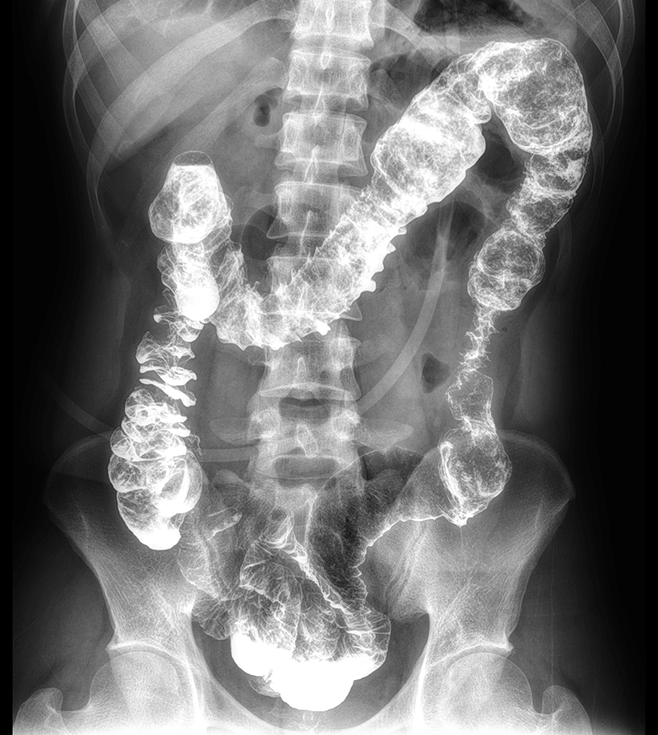

專業的影像處理系統

“騰靈”系列搭載的IEAE影像處理系統,具備多項發明專利。本系統采用多頻域圖像處理技術,其6大核心處理模塊使影像具有優秀的一致性、柔和性、空間層次感和紋理細膩度,為用戶精準診斷病灶奠定了堅實的基礎。

iGCR

智能感興趣區

灰度補償 -

iTE

智能組織

均衡 -

iCED

智能增強

降噪 -

iMR

智能金屬

識別 -

iDG

智能柵紋

去除 -

iDC

智慧劑量

控制